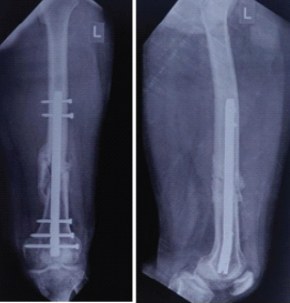

Figure 4: Anteroposterior and lateral views at 6 months showing distal third fracture of the femur with retrograde nail.

Out of all study participants, 58 patients had closed fractures and rest 2 patients had compound fractures. The mean operation-injury interval was 5.5 ± 0.67 days for antegrade nailing and 5.8 ± 0.65 days for retrograde nailing. The mean duration of the surgery was 85 ± 2.15 min for retrograde nailing and 95 ± 1.39 min for antegrade nailing. Mean time for radiological union with retrograde nailing was 10 ± 0.38 weeks (Fig. 1, 2, 3, 4) and with antegrade nailing, it was 14 0.44 weeks (Fig. 5, 6).